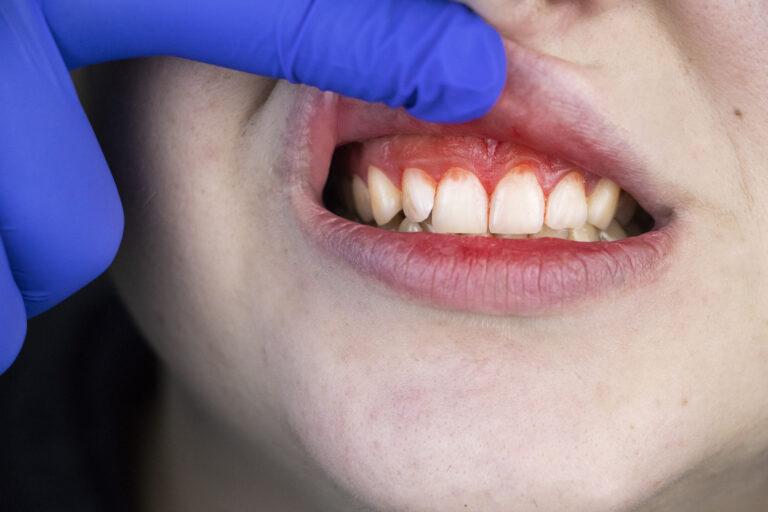

Leczenie kanałowe jest jedną z najczęściej wykonywanych procedur w gabinetach stomatologicznych. Procedura ta polega na usunięciu zakażonej lub uszkodzonej miazgi z wnętrza zęba, a następnie wypełnieniu powstałej przestrzeni specjalnym materiałem. Leczenie kanałowe pozwala uratować ząb, który w przeciwnym razie musiałby…